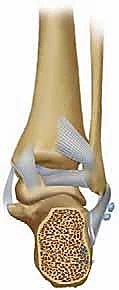

المفصل تحت الكاحل هو مفصل زلالي معقد يسمح بحركتي الانقلاب الداخلي (Inversion) والانقلاب الخارجي (Eversion). أي خلل في تطابق الأسطح الغضروفية لهذا المفصل بمقدار ملليمترات قليلة يؤدي إلى احتكاك غير طبيعي، تآكل سريع للغضروف، وتطور التهاب المفاصل التنكسي (Osteoarthritis) المؤلم.